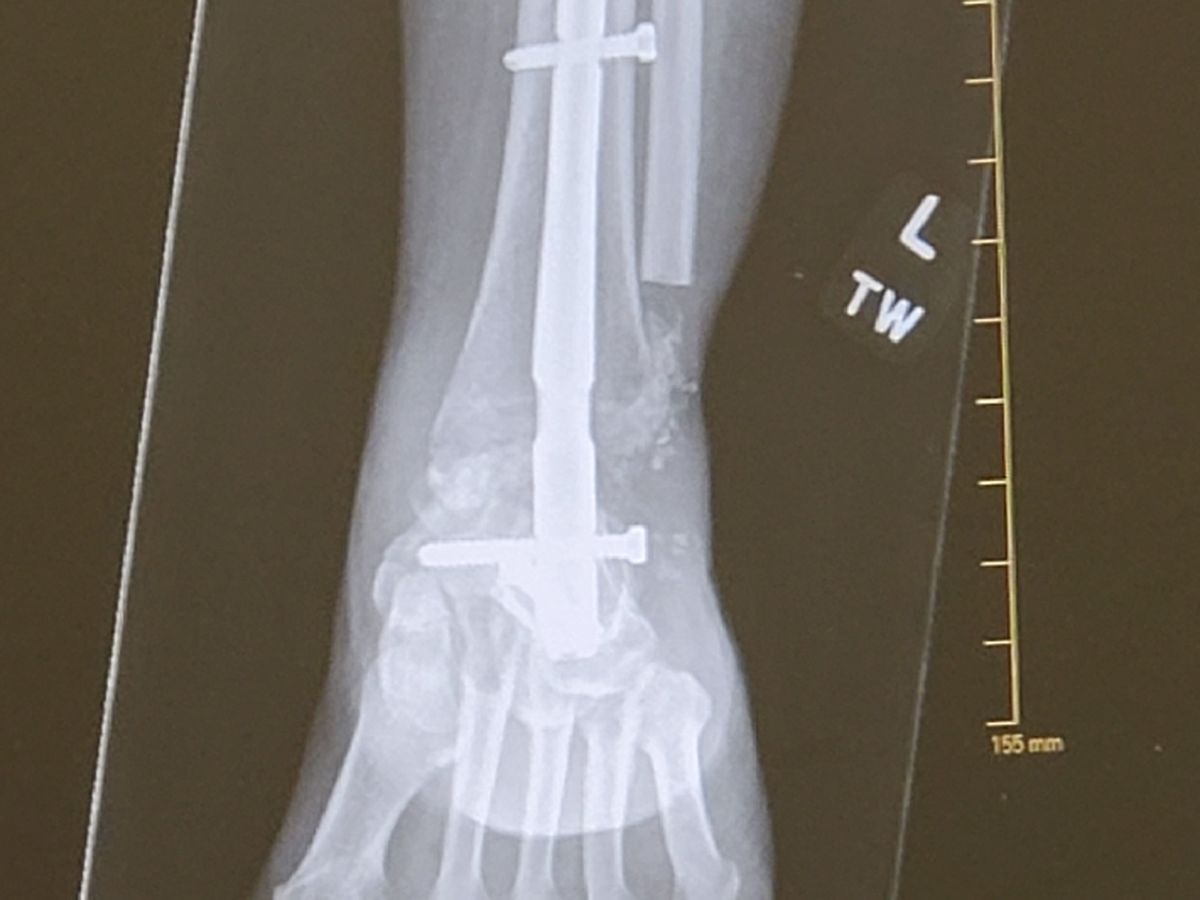

On Saturday, May 30th, My sister Donna was in a bad motorcycle accident. She sustained extensive injuries and was air lifted to OSF in Peoria. She has multiple broken bones & fractures. She has had 3 surgeries since the accident, 2 on leg , 1 on her pelvis. She will need several more surgeries. Donna does not have any insurance. The hospital bills are going to be very high and she is not able to work. My sister is one tuff cookie and get through this. Please show support for her long journey to recovery. No amount is to small. Thank-you from the bottom of our hearts for the prayers, texts and calls.